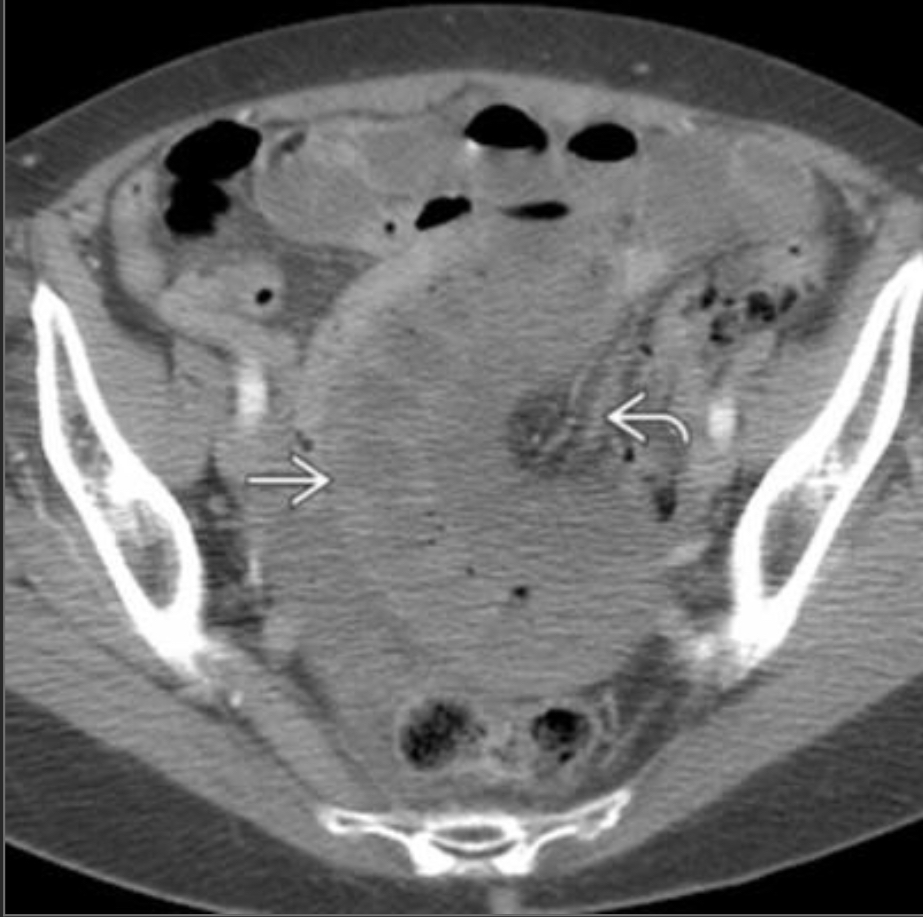

54F with abdominal pain, n/v

Closed loop obstruction

There is a cluster of fluid-distended loops of small bowel in the pelvis that are notable for relative absence of intraluminal gas, minimal enhancement of their mucosa, infiltrated mesentery, engorged mesenteric vessels and interloop ascites. The distal small bowel is of normal caliber.

—> findings suggestive of ischemia/closed loop include minimal enhancement of the mucosa and engorged mesenteric fat/vessels, and focal ascites.

—> in pt w/appropriate hx could also be a post-op intramesenteric hernia